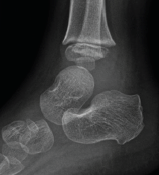

Nida Blankas-Hernaez, MD, FAAP; Angela C. Tang; Samir S. Dengle, BSc

A 3-year-old boy presented to the emergency department for the fourth time in 8 days, this time for left ankle and foot swelling.

08/20/2015